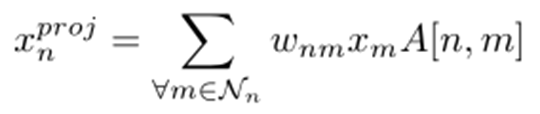

首先利用收集到的特征图创建特征交互空间,构造交互图G = {V, E, a},其中V表示交互图中节点的集合,E表示交互节点之间的边,a表示邻接矩阵。给定一个学习到的高维特征X = {xn}N n=1∈RN×C和来自主干网络的Xn∈R1×C,首先将原始特征投影到特征交互空间上,生成投影特征XPROJ= {xproj N}N n=1∈RK×C’。K为交互图中交互节点的个数,C’为交互空间维数。简单的方法产生每个元素xproj n∈XPROJ, n ={1,…, K}使用其相邻元素的线性组合:

其中Nn相邻体素n。朴素方法通常采用具有冗余连接和交互节点间参数的全连通图,很难进行优化。更重要的是,线性组合方法缺乏自适应采样的能力,因为不同的图像包含不同的脑胶质瘤上下文信息(如位置、大小和形状)。作者采用自适应采样策略来解决这个问题: